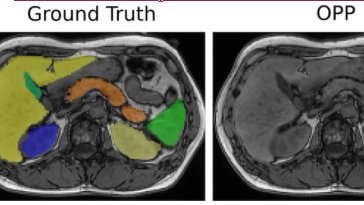

Got the 🔥🔥 when hallucination-free organ segmentation is the vibe! 🤩 Researchers Christian Wachinger & Anne-Marie Rickmann have made it possible with #OrganResectionSurgery #ComputerVision #DeepLearning - Read all about it: deepai.org/publication/ha…